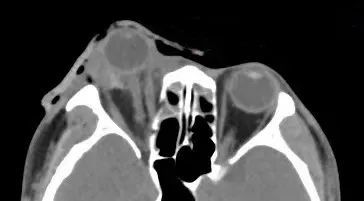

据厦门眼科中心眼外伤及眼底病二科副主任医师吴东海回忆,接诊时,陈先生的右眼眼球脱出眼眶,肿胀充血,眼睛无法正常闭合。他的视力几乎丧失,眼球上下方都有大面积的结膜裂伤。

辅助检查的影像学结果显示,陈先生的伤眼近一半已脱出眼眶,眼球壁上还有星星点点的异物存留。

眼球脱出的医学影像示例

所幸陈先生视神经、眼外肌肉未发生断裂,眼球壁也未破裂,但他的状况依然危急。为防止角膜长时间暴露,医生立即对陈先生的伤眼做了包扎处理。待陈先生的身体状况稳定后,医生通过手术将陈先生的眼球还纳。